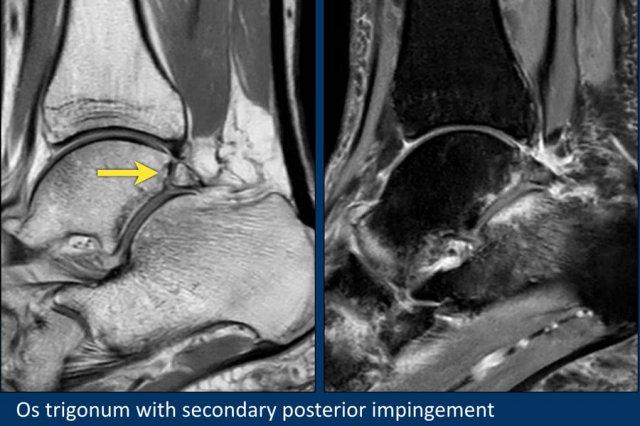

Đây là một bệnh nhân khác có os trigonum.

Trên các chuỗi xung fatsat, có phù nề ở os trigonum và các mô mềm xung quanh.

Đây là một ví dụ về hội chứng chèn ép phía sau do os trigonum có triệu chứng.